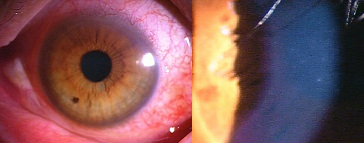

今日いらした24歳女性の症例です。

強い充血を認めます。写真の右側は、はやり目に特徴的な後遺症で、黒目(角膜)が濁っている写真です。もう少し分かりやすい、ヒドイ症例の写真を出したいのですが、ヒドイ症例は第一診察室には入らないようにしていただいたり、写真をとるなどの、余分な時間を少しでも省いて診療を行い、院内感染を予防する必要があり、なかなか難しいのです。